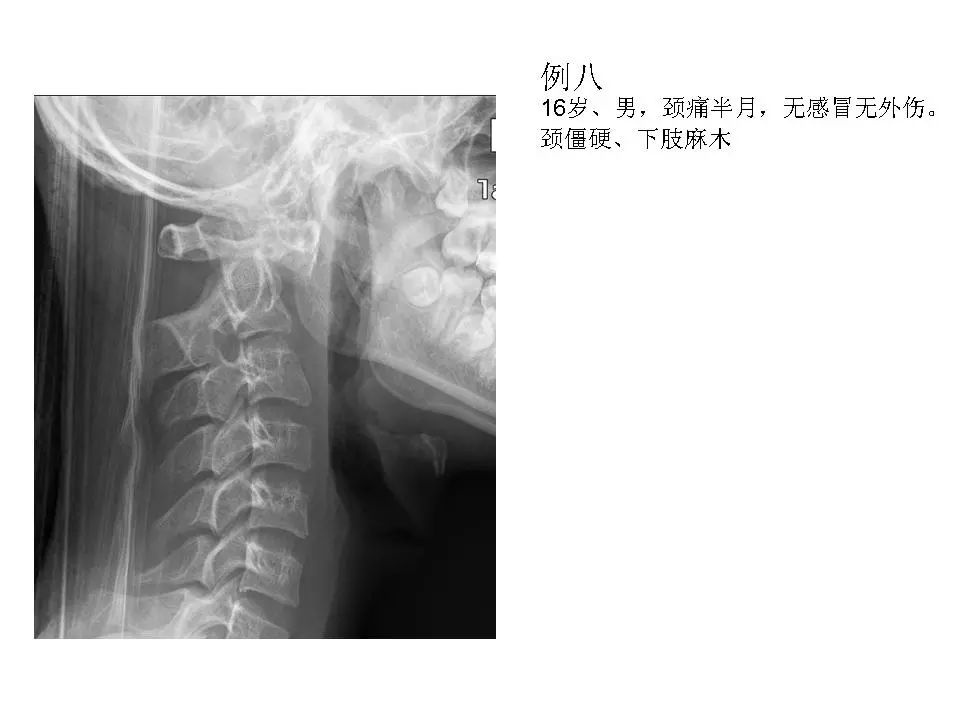

寰枢关节脱位的影像诊断